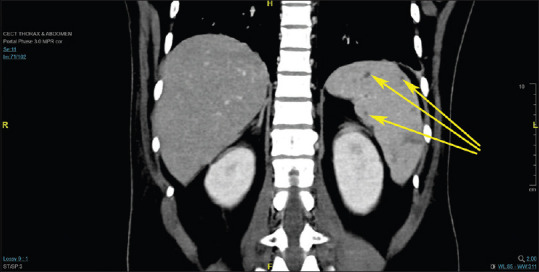

Melioidosis is a disease endemic to India but often goes unrecognized, leading to considerable illness and death. We present the case of a 31-year-old man who had a fever of unknown origin, abnormal renal and liver function tests, and negative tests for dengue, typhoid, leptospirosis, and scrub typhus. Imaging revealed multiple splenic infarcts. Initially suspected to be malaria due to its prevalence in South India, further investigation uncovered pneumonia along with several liver and splenic abscesses, raising the possibility of melioidosis. Blood culture eventually identified Burkholderia pseudomallei, confirming the diagnosis. As malaria cases decline in Southeast Asia, emergency physicians should consider melioidosis in their differential diagnosis of acute febrile illnesses, especially in endemic areas. Early detection and prompt antibiotic treatment are vital for managing this often under-recognized disease with a high fatality rate. Thus, melioidosis should be considered in patients with unexplained fever in endemic regions, as early diagnosis and intervention can be life-saving.